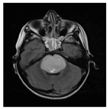

Among patients included in the PEDIAMODECAN program (seven DIPGs and four tHGGs (thalamic high-grade gliomas)), we selected four cases that were mismatch repair proficient and harboring the driver histone mutation H3.3 K28M. We were able to derive four PDCLs out of seven DIPGs and two PDCLs out of four tHGGs. Among the four DIPG PDCLs, we had only two H3.3-K28M-mutated tumors. The patient ages ranged from 9 to 18 years old. The clinical reports, including immunohistochemistry results, are summarized in Table 1. MRI radiological data showed that DIPGs and tHGGs invaded the pons or thalamus, respectively, at diagnosis, with a localized tumor enhancement after gadolinium injection on T1-weighted and T2-weighted FLAIR (fluid-attenuated inversion recovery) sequences. The immunohistochemical analyses were performed for Ki67, GFAP (glial fibrillary acidic protein), p53, EGFR (epidermal growth factor receptor), PTEN (phosphatase and tensin homolog), Olig2 (oligodendrocyte transcription factor 2), and HIF-1α (hypoxia inducible factor 1 alpha) biomarkers.

Table 1.

Clinical characteristics of four pediatric H3F3A-K28M-mutated high-grade gliomas. BT: brain tumors; HGG: grade IV glioma; DIPG: diffuse intrinsic pontine glioma; Iri/Beva: Irinotecan/Bevacizumab; ADC: apparent diffusion coefficient measured within T2-weighted injected sequences. Ki67, HIF1 (hypoxia inducible factor 1), GFAP (glial fibrillary acidic protein), EGFR (epidermal growth factor receptor), PTEN, and Olig2 stainings (% of positive cells in tumor specimen) were used. Tumors for which analyses were unavailable are designated NA (not available).* Stupp protocol with a total of 12 courses of temozolomide was used in post-radiotherapy.